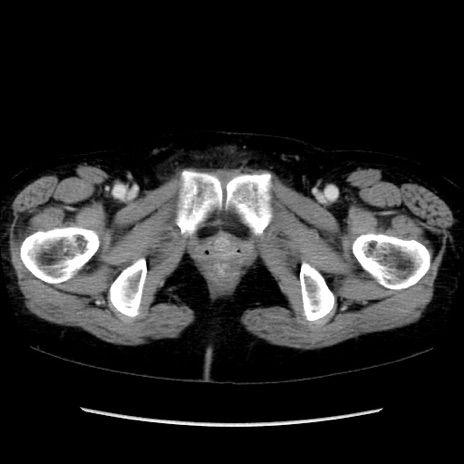

症例32(横断像)

【症例】40歳代 女性

【主訴】上腹部痛、嘔気・嘔吐

【現病歴】約9時間前頃から急に上腹部痛、嘔気、嘔吐が出現。改善しないため救急要請。

【既往歴】子宮頚癌(広汎子宮全摘術、放射線療法)、腸閉塞

【身体所見】腹部:平坦、軟、腸雑音亢進、上腹部を中心に腹部全体に圧痛あり。

【データ】WBC 8400、CRP 0.03